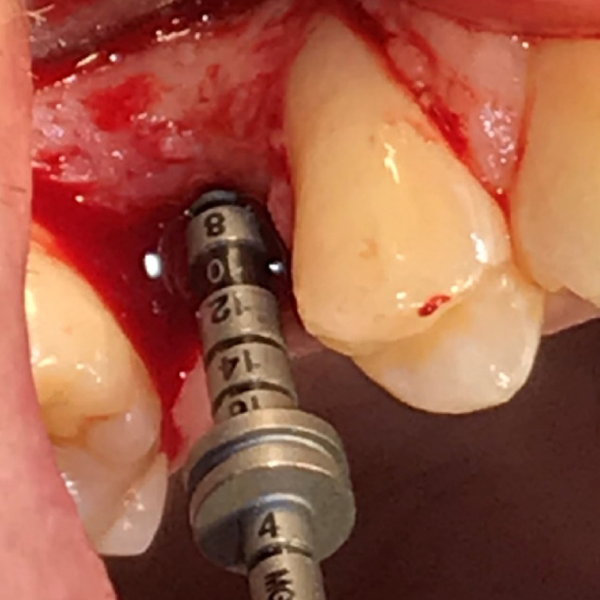

Patient suffered from localised periodontitis affecting all lower incisors with severe bone loss.